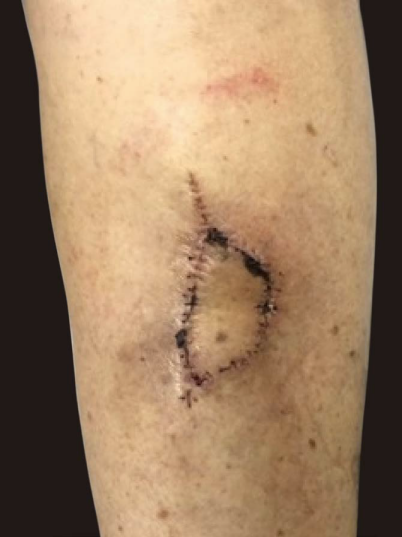

Paciente feminina, 92 anos, apresentando lesão nodular hiperceratótica de aproximadamente 2cm no maior diâmetro na face anterior da perna esquerda com biópsia evidenciando carcinoma espinocelular in situ (Figura 1), sem tratamentos prévios. Submetida à cirurgia micrográfica de Mohs, livre de tumor no primeiro estágio (Figura 2). Para fechamento primário, foi utilizada a técnica Keystone, com uma aba curvilínea de mesma largura do defeito e com ângulos de 90º nos cantos da área de exérese do tumor. Avançando a aba no defeito primário, resulta num defeito secundário que é mais longo e estreito. Perpendiculares ao avanço do retalho, as duas bordas periféricas foram avançadas em V-Y e a aba, avançada sobre o defeito, sendo suturado com fio nylon 4-0 (Figuras 3 e 4). A paciente apresentou boa evolução, sem complicações pós-operatórias (Figura 5).